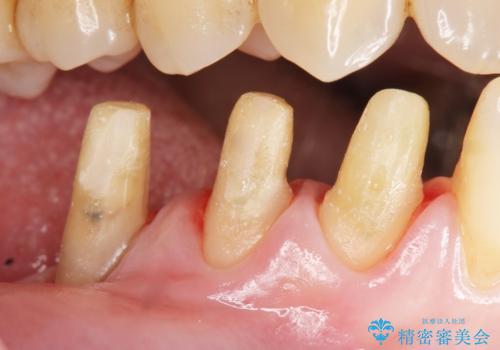

- 下の前歯(左下2)と奥歯の動揺がひどくなってきたことを主訴に来院された患者様です。

精査したところ、前歯の咬み合わせが反対になっていること、下の奥歯(下顎両側67)が4本欠損していることから動揺が生じていました。

入れ歯も抵抗があるとのことから、相談を重ね、今の状態では保存不可能な下の前歯(左下2)を抜去し、ブリッジや連結補綴により動揺を抑えることにしました。